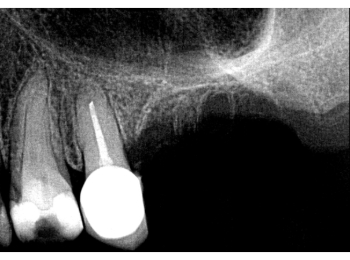

Röntgen Krone distal

25: apikal aufgehellt, Krone distal undicht, WF reicht nicht bis ins untere Drittel.

26 und 27 nicht erhaltungswürdig, vertikaler Knocheneinbruch.